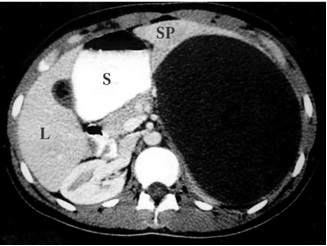

הטומוגרפיה הממוחשבת עשויה לסייע באבחון מהות השאת בצורה עקיפה, למשל על-ידי גילוי שאת בלבלב עם גרורות בטחול. הטומוגרפיה הממוחשבת אינה מזהה תהליכים בטחול הקטנים מ- 1 ס"מ. אולם, גם בבדיקה של טחול תקין קיים חוסר הומוגניות לאחר הזרקת חומר הניגוד. כיסית רגילה נראית בטומוגרפיה ממוחשבת כגוש עגול, סמיך כמו נוזל, עם גבול חד (תצלום 3.11). המטומה לרוב קשה לאבחון, כי סמיכותה קרובה לזו של הרקמה שמסביבה. אוטם עשוי להופיע בצורה האופיינית של מניפה.